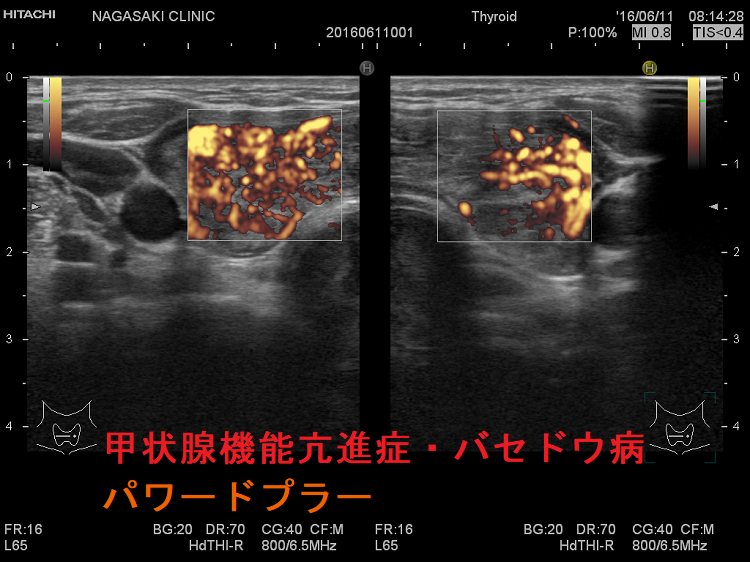

甲状腺機能亢進症・バセドウ病

甲状腺機能亢進症・バセドウ病 通常ドプラー

甲状腺機能亢進症・バセドウ病 通常ドプラーモード

甲状腺機能亢進症・バセドウ病 パワードプラー

甲状腺機能亢進症・バセドウ病 パワードプラー;通常ドプラーモードよりも感度が高いです。

甲状腺機能亢進症バセドウ病 火炎状血流増加

甲状腺機能亢進症/バセドウ病の火炎状血流増加;著明な血管増殖のため甲状腺内の血流が増加します。

しかし、無痛性甲状腺炎でも、甲状腺機能低下症でも血流増加するため、これだけでは鑑別できません。

甲状腺機能亢進症 バセドウ病 火炎状血流増加

甲状腺機能亢進症/バセドウ病の火炎状血流増加